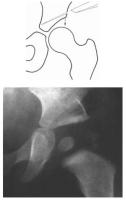

Abbildung 11: Prinzip der Acetabuloplastik. Schräges Einmeiseln am Pfannendach, wobei der Pfannendachanteil zur Korrektur nach kaudal gedrückt wird. Der eingefügte Knochenkeil ist nach der Korrektur deutlich sichtbar.